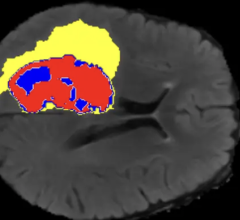

May 01, 2025 — Researchers from the Rajpurkar Lab in the Department of Biomedical Informatics at Harvard Medical School ...